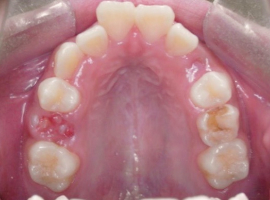

上顎

- Before